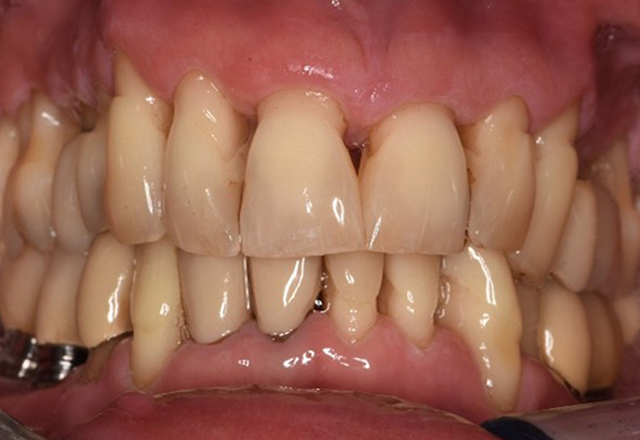

Der gesunde Patient mit parodontaler Vorerkrankung & Periimplantitis

Ein 52-jähriger Patient stellt sich zur Präventionssitzung vor. Der Patient hat keine Allgemeinerkrankungen und nimmt keine Medikamente ein. Er hat verschiedene zahnärztliche Versorgungen und zudem zwei aktive kariöse Läsionen. Außerdem verfügt der Patient über vier Implantate (2., 3. und 4. Quadrant). Es zeigt sich eine parodontale Vorerkrankung (Stadium IV, Grad B). Derzeit herrschen stabile parodontale Verhältnisse, lediglich am Implantat regio 36 zeigen sich Sondierungstiefen (ST) von 5 mm. Zudem lässt sich eine Gingivitis feststellen. mehr Infos

Die gesunde Patientin mit parodontaler Vorerkrankung

Die 68-jährige Patientin hat keine zahnmedizinisch relevanten allgemeingesundheitlichen Vorerkrankungen oder Medikation, auch aus dem Lebensstil ergibt sich kein besonderes Risiko. Die Patientin hat zwei Implantate (3. Quadrant, seit fünf Jahren) sowie eine parodontale Vorerkrankung (Parodontitis Stadium IV, Grad B) mit Zahnverlust. Derzeit zeigen sich stabile parodontale Verhältnisse. Für die Prophylaxesitzung ergeben sich vier Empfehlungen in den Bereichen Anamnese/Befund, Motivation/Instruktion, der Wahl der geeigneten Instrumente und für Resümee/Folgetermin. mehr Infos

NIWOP – No Implantology without Periodontology